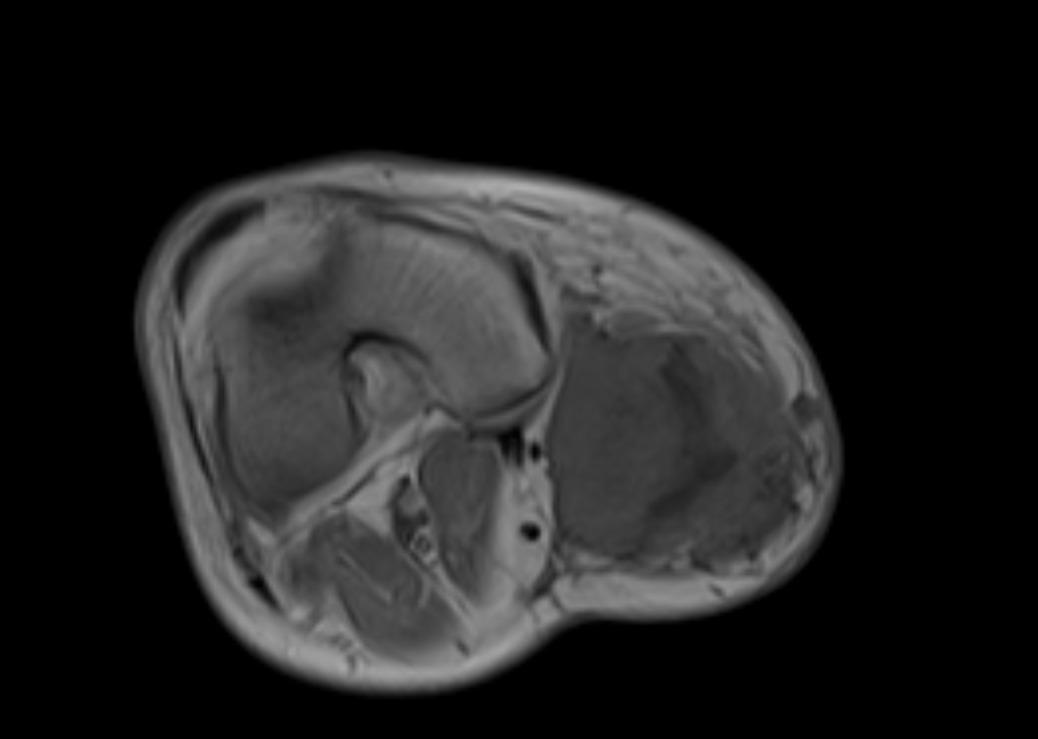

Muscle Cancer